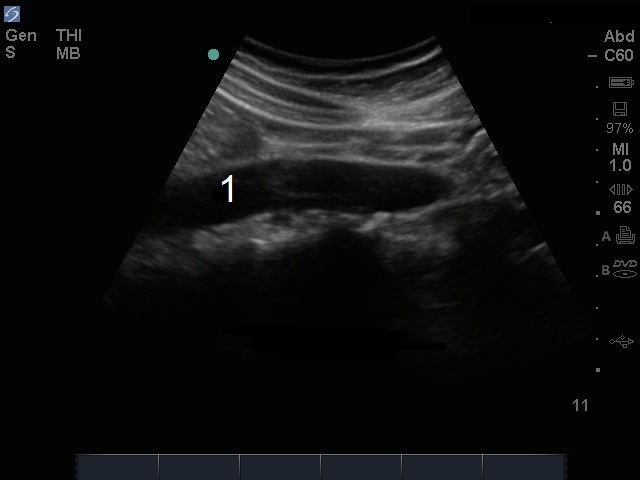

M-Turbo: Aorta distal - Imagen sagital

M-Turbo: Aorta distal - Vista longitudinal

Aorta